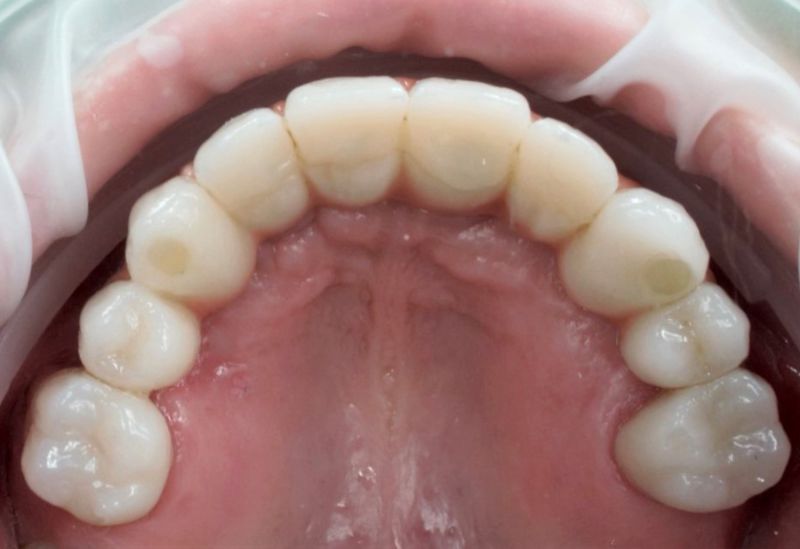

Samodzielna korona nie obciążająca zębów sąsiednich - to dzisiaj możliwe.

+ brak konieczności szlifowania zębów

+ brak zalegania resztek pokarmowych pod mostem